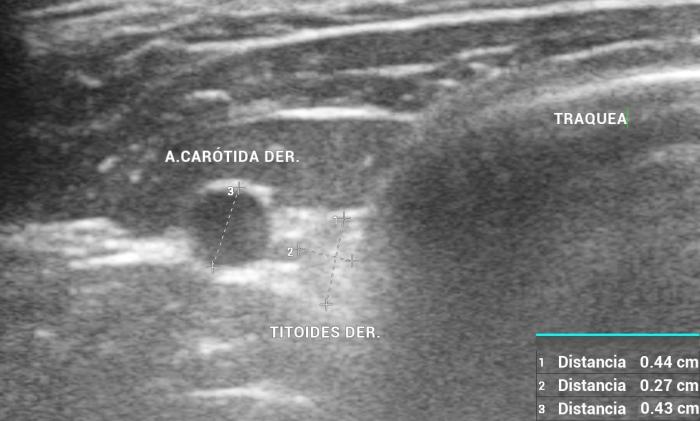

El índice TG/CCA es una herramienta ecográfica cuantitativa propuesta para la evaluación del tamaño tiroideo en perros, particularmente útil cuando se sospecha de hipoplasia glandular o hipotiroidismo12. Este índice se calcula mediante la medición del área transversal del lóbulo tiroideo (TG) y la comparación con el área de la arteria carótida común (CCA) adyacente, ambas obtenidas en un corte transversal a nivel medio cervical8.

Para su obtención, el animal se posiciona en decúbito dorsal con el cuello extendido. Se utiliza un transductor lineal de alta frecuencia (mínimo 10 MHz), y se realiza una imagen transversal donde se identifican claramente el lóbulo tiroideo y la arteria carótida. Se mide el área de cada estructura mediante trazo elíptico o libre, dependiendo de la morfología. La relación se expresa como TG/CCA, un valor adimensional que permite estandarizar la evaluación tiroidea en animales de distinto tamaño corporal7.

En perros clínicamente sanos, se ha reportado un valor promedio de TG/CCA de 1.53 en promedio12. Valores consistentemente bajos pueden sugerir atrofia glandular o hipoplasia, siendo útiles para apoyar el diagnóstico de hipotiroidismo en pacientes con hallazgos clínicos y laboratoriales compatibles. Según Sasaki et al. (2020), si se utiliza el valor de corte <1.12, el índice TG/CCA indica hipotiroidismo con una sensibilidad del 100 %, una especificidad del 83 % y una precisión del 90 %.

Este índice se ha mostrado reproducible, poco afectado por el tamaño corporal o la edad, y puede ser una herramienta de utilidad en estudios longitudinales o de seguimiento terapéutico. Si bien su uso no reemplaza las pruebas hormonales específicas, constituye un complemento objetivo y no invasivo dentro del algoritmo diagnóstico ecográfico de la glándula tiroides en perros4.

El uso de estructuras vasculares adyacentes como referencias anatómicas ha sido una estrategia útil en ecografía veterinaria para estandarizar las mediciones de órganos pequeños como la glándula tiroides. En este contexto, Bandula Kumara et al. (2019) propusieron la medición de la relación entre el diámetro tiroideo (TD) y el diámetro de la arteria carótida común (CCA) como una forma práctica de evaluar el tamaño de la glándula en perros clínicamente normales (Figura 5A-B).

Los autores realizaron un estudio en el que midieron el diámetro anteroposterior de los lóbulos tiroideos y el diámetro externo de la CCA en cortes transversales obtenidos a nivel del cuello medio. Encontraron que esta relación se mantiene relativamente constante entre razas y tamaños corporales, sugiriendo que puede ser utilizada como parámetro de referencia ecográfica. Específicamente, en perros adultos sanos, la relación TD/CCA fue de 1.74 ± 0.40 (rango 1.11–2.43)6. Si los valores se encuentran por debajo del rango normal pueden ser considerados potencialmente indicativos de hipoplasia tiroidea o atrofia glandular.

Una ventaja de esta relación es que la arteria carótida común es fácilmente identificable ecográficamente, presenta un diámetro estable y poco variable en condiciones fisiológicas, y se ubica en estrecha proximidad con la glándula tiroides. Esto la convierte en una excelente estructura de referencia para normalizar mediciones entre individuos de diferente tamaño corporal, permitiendo evaluaciones objetivas en poblaciones mixtas de perros de compañía.